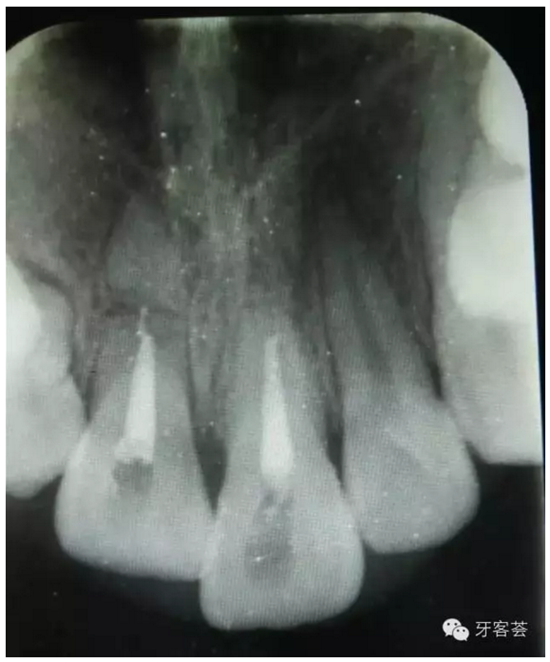

圖4:根充完成后,11根尖橫折。21根尖橫折部分已經(jīng)骨化。擬行11根尖斷根取出術(shù)及12拔除。